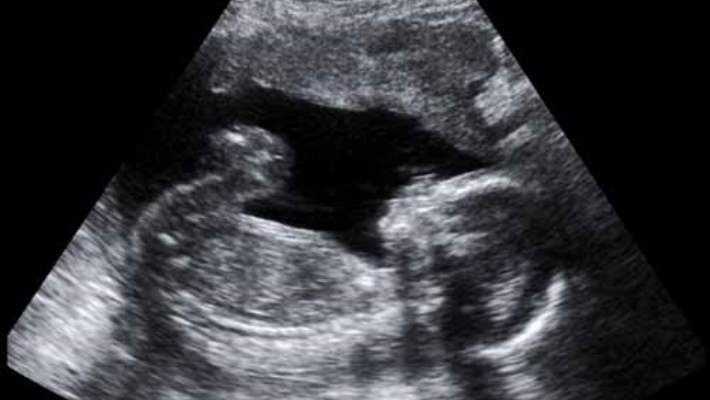

Düşükten ne kadar sonra yeniden deneyebiliriz? Düşük yapan kadınların doktorlarına sordukları ilk sorulardan biri bu. Ve yeni bir araştırma kadınların düşükten sonra yeniden hamile kalmak için beklemelerine gerek olmadığını iddia ediyor. Bu yeni araştırmaya göre, kadın düşük sonrasında ne kadar erken hamile kalırsa sağlıklı bir hamilelik geçirme şansı o kadar yüksek.

Özellikle düşükten sonraki altı ay içinde hamile kalmak yeni bir düşük riskini ya da hamilelikle ilgili başka bir sorun yaşama ihtimalini uzun süre bekleyen kadınlara oranla çok daha azaltıyor.

Yeni araştırma ilk hamileliklerindeki düşükten hemen sonra hamile kalan 30.937 kadını inceledi. Uzmanların elinde ilk hamilelikteki düşüklerin sebeplerine ilişkin bilgiler yoktu.